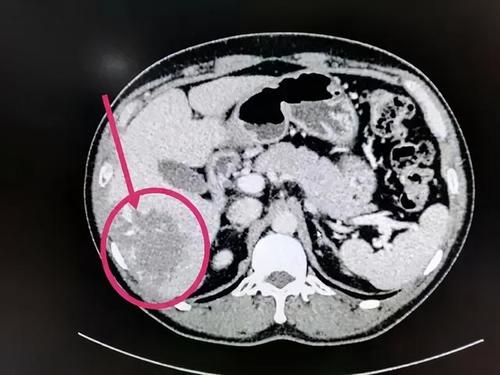

从形态上看肝血管瘤分小毛细血管瘤和巨大肝血管瘤。毛细血管瘤小于5厘米,巨大肝血管瘤大于5厘米。按照分型可分肝海绵状血管瘤、肝硬化性血管瘤、肝毛细血管瘤、肝血管内皮细胞瘤。

肝内血管瘤一般不会引起症状,多在影像检查时被发现。所以勿需特殊处理。但是如果血管瘤内出现凝血或外伤后破裂出血时应进行手术治疗。巨大血管瘤可引起血小板减少和凝血功能变化,或压迫肝脏造成肝功损害或门脉高压,也需手术切除。